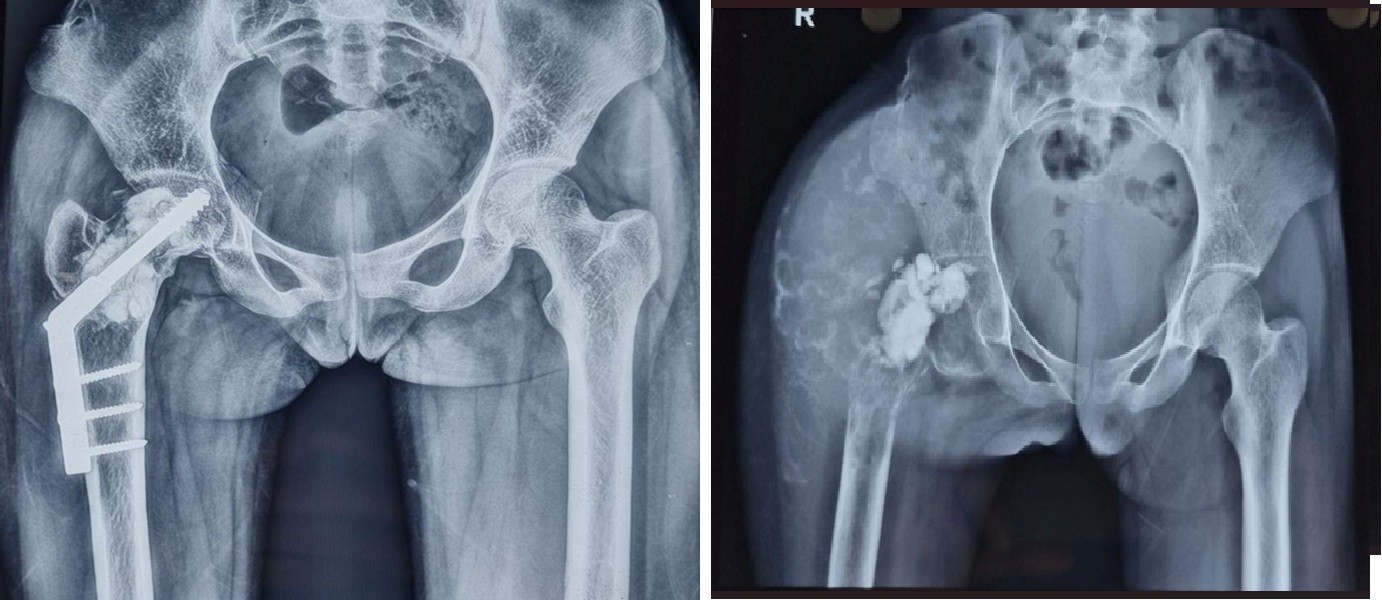

A 21-year-old female presented with complaints of pain and swelling in the right proximal thigh and hip, accompanied by an inability to bear weight. The patient had been apparently well 4 years earlier when she sustained a pathological fracture of the proximal femur and was diagnosed with a GCT (Fig. 1).

Figure 1: Giant cell tumor involving the neck region of the femur with pathological fracture.

She underwent surgery involving curettage, bone cement filling, and dynamic hip screw fixation at another institution (Fig. 2). However, the patient experienced a recurrence of the tumor 2 years later, prompting removal of the implant by the primary surgeon.

Figure 2: Initial treatment included curettage, cement filling, and dynamic hip screw fixation. Following tumor recurrence, the implant was removed.